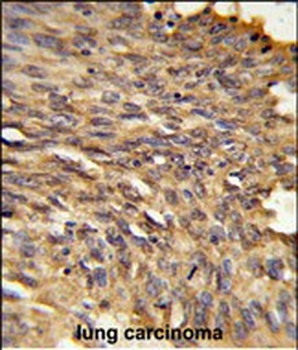

IHC-P, WB

应用稀释比例:WB: 1:1000, IHC-P: 1:50-100